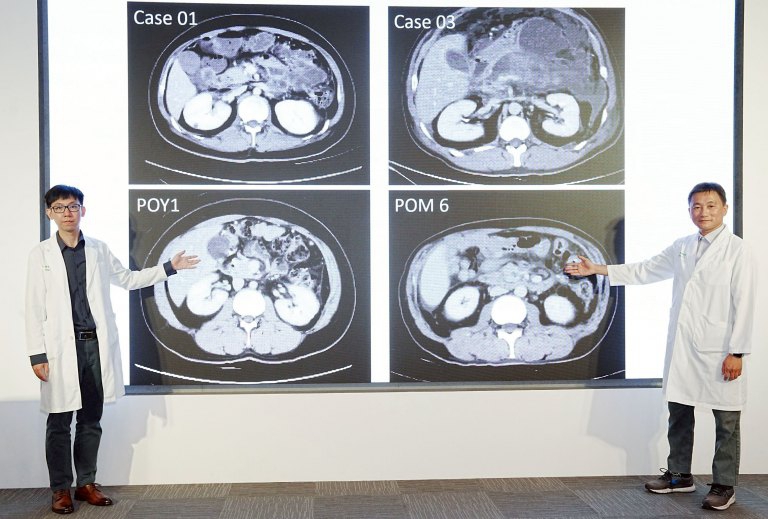

中國醫藥大學附設醫院指出,近期收治一名39歲男性患者,因持續上腹疼痛就醫,經檢查診斷為膽結石引發之急性壞死性胰臟炎。醫療團隊採取分階段整合治療策略,在穩定病況後進行微創處置,患者術後恢復良好,已回復日常生活。

院方說明,壞死性胰臟炎治療近年已逐步由傳統開腹手術,轉向「延遲介入、優先微創」的整合照護模式。鄭智忠表示,此類疾病變化迅速,且可能出現出血或器械相關併發症,需仰賴跨專科團隊即時評估與處置,以降低治療風險。

該院胰臟醫療團隊在葉俊杰帶領下,針對壞死性胰臟炎患者採用分階段治療,包括初期穩定生命徵象、影像導引經皮引流、內視鏡介入,以及必要時進行微創清創手術。院方表示,相關治療策略有助於降低侵入性與併發症風險,提升整體照護成效。

統計顯示,該團隊近一年收治多例重症壞死性胰臟炎患者,病因涵蓋膽結石、酒精使用及高三酸甘油脂等,經多專科協作治療後,多數患者病況獲得控制並逐步康復,其餘病例仍持續追蹤治療中。